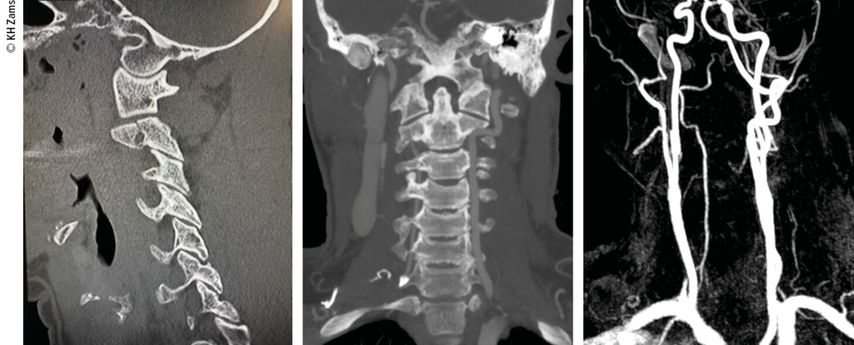

Abb. 3: Mann, 30a, Z.n. Snowboardsturz, Rotations-/Subluxationsverletzung C5/6 mit Dissektion der A. vertebralis r.; Zervikobrachialgie mit sensiblem Defizit; OP unter Heparintherapie, APT für 3 Monate